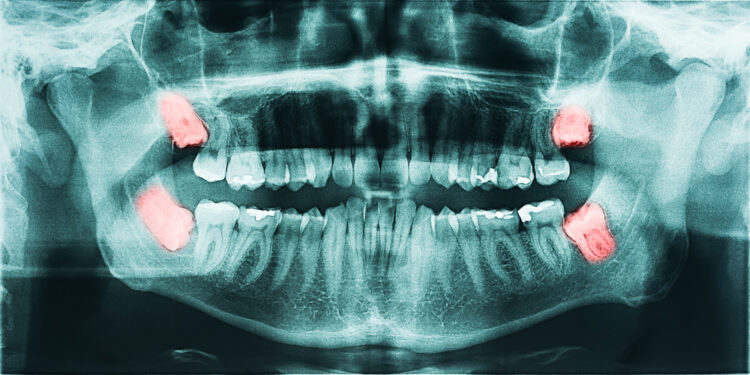

Norint įvertinti protinio danties būklę, pirmiausia atliekamas apžiūrėjimas ir išklausomi jūsų nusiskundimai. Tiksliai nustatyti dantų padėtį ir pokyčius žandikaulyje leidžia rentgeno nuotraukos – jos parodo, ar dantys įstrigę, ar pažeisti kiti dantys ar žandikaulis.